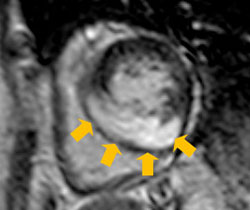

• 図1:シネ画像(水平断):肥大型心筋症の症例

心室中隔に非対称性の壁肥厚を認める。